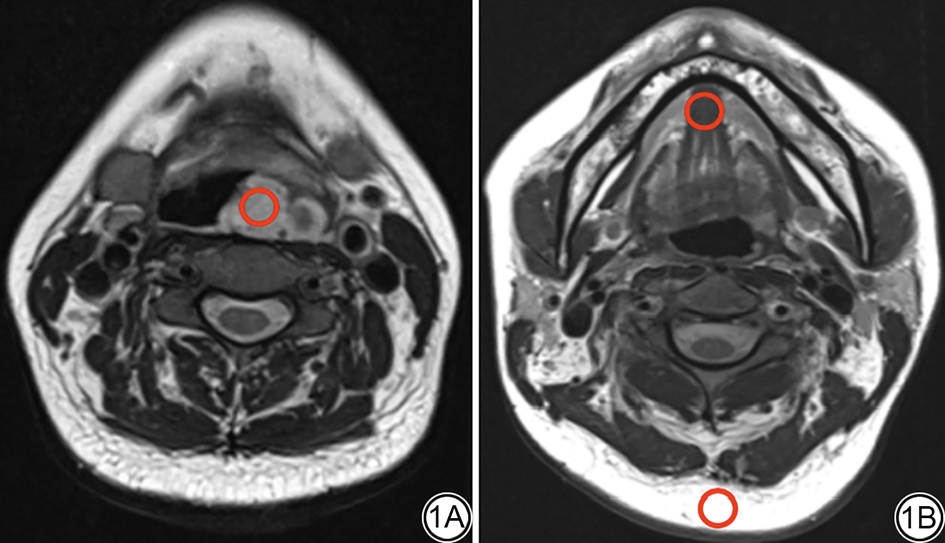

所有患者的标准T1WI、标准T2WI-Dixon序列及DL-T1WI、DL-T2WI-Dixon序列图像质量均满足诊断要求。两位医生对8组图像的整体图像质量、伪影和病变显示清晰度的主观评分一致性非常好,标准T1WI、DL-T1WI、标准T2WI-Dixon-Water像、标准T2WI-Dixon-Inphase像、标准T2WI-Dixon-Fat像、DL-Dixon-Water像、DL-Dixon-Inphase像和DL-Dixon-Fat像的Kappa值分别为0.88(0.73~1.00)、0.87(0.71~1.00)、0.84(0.73~0.93)、0.80(0.60~0.96)、0.91(0.80~0.98)、0.87(0.76~0.96)、0.84(0.65~0.96)、0.91(0.78~1.00)。DL-T1WI和DL-T2WI-Dixon序列与标准T1WI和标准T2WI-Dixon序列在整体图像质量、伪影和病变显示清晰度方面差异无统计学意义(P均>0.05),详见表2表3图2

图2  男,63岁,因舌根部发现肿物3周来院检查。标准T1WI序列(2A)、标准T2WI-Dixon-Inphase序列(2B)、Water序列(2C)和Fat序列(2D)和DL-T1WI序列(2E)、DL-T2WI-Dixon-Inphase序列(2F)、Water序列(2G)和Fat序列(2H)均能够清晰显示病变,整体图像质量优秀。T1WI:T1加权成像;T2WI:T2加权成像;DL:深度学习。

Fig. 2  A 63-year-old male presented with a tongue tumor discovered 3 weeks prior and underwent examination at our hospital. The standard T1WI sequence (2A), standard T2WI-Dixon-Inphase sequence (2B), Water sequence (2C), and Fat sequence (2D), as well as the DL-T1WI sequence (2E), DL-T2WI-Dixon-Inphase sequence (2F), Water sequence (2G), and Fat sequence (2H), all clearly visualized the lesion, with overall excellent image quality. T1WI: T1 weighted imaging; T2WI: T2 weighted imaging; DL: deep learning.